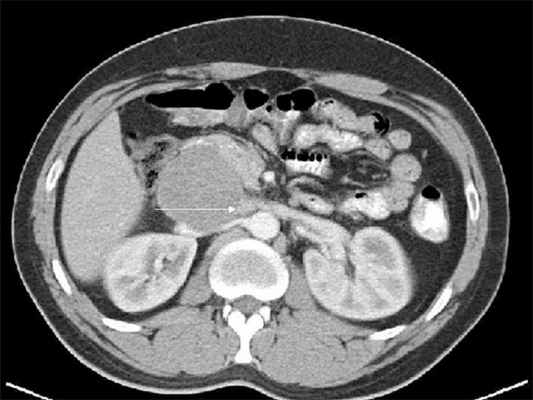

- Компьютерная томография брюшной полости с болюсным внутривенным введением контрастного вещества помогает отграничить неизмененную паренхиму от опухолевых очагов, которые не накапливают контраст. Компьютерная томография имеет высокую информативность и обеспечивает обнаружение опухолей в 95% случаев.

Ультразвуковая эхография помогает определить размеры и глубину расположения опухоли, выяснить ее связь с сосудами; компьютерная томография позволяет определить опухоли диаметром начиная с 1,5-2,0 см, точное их распространение, топографию, обнаружить увеличение лимфатических узлов.